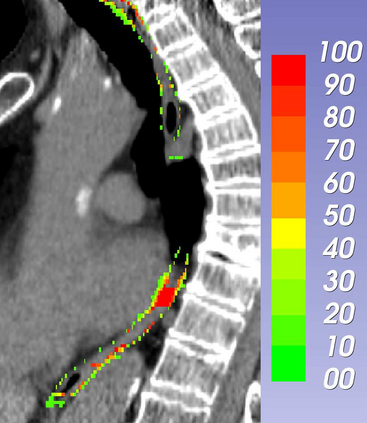

Stereotactic body radiation therapy allows for a precise and accurate dose delivery. Organ motion during treatment bears the risk of undetected high dose healthy tissue exposure. An organ very susceptible to high dose is the oesophagus. Its low contrast on CT and the oblong shape renders motion estimation difficult. We tackle this issue by modern algorithms to measure the oesophageal motion voxel-wise and to estimate motion related dosimetric impact. Oesophageal motion was measured using deformable image registration and 4DCT of 11 internal and 5 public datasets. Current clinical practice of contouring the organ on 3DCT was compared to timely resolved 4DCT contours. The dosimetric impact of the motion was estimated by analysing the trajectory of each voxel in the 4D dose distribution. Finally an organ motion model was built, allowing for easier patient-wise comparisons. Motion analysis showed mean absolute maximal motion amplitudes of 4.24 +/- 2.71 mm left-right, 4.81 +/- 2.58 mm anterior-posterior and 10.21 +/- 5.13 mm superior-inferior. Motion between the cohorts differed significantly. In around 50 % of the cases the dosimetric passing criteria was violated. Contours created on 3DCT did not cover 14 % of the organ for 50 % of the respiratory cycle and the 3D contour is around 38 % smaller than the union of all 4D contours. The motion model revealed that the maximal motion is not limited to the lower part of the organ. Our results showed motion amplitudes higher than most reported values in the literature and that motion is very heterogeneous across patients. Therefore, individual motion information should be considered in contouring and planning.